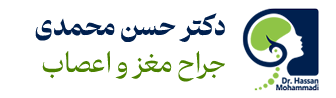

MRI مغز و مسیر بینایی

دقیقترین روش برای بررسی اندازه، محل و نحوه انتشار تومور.